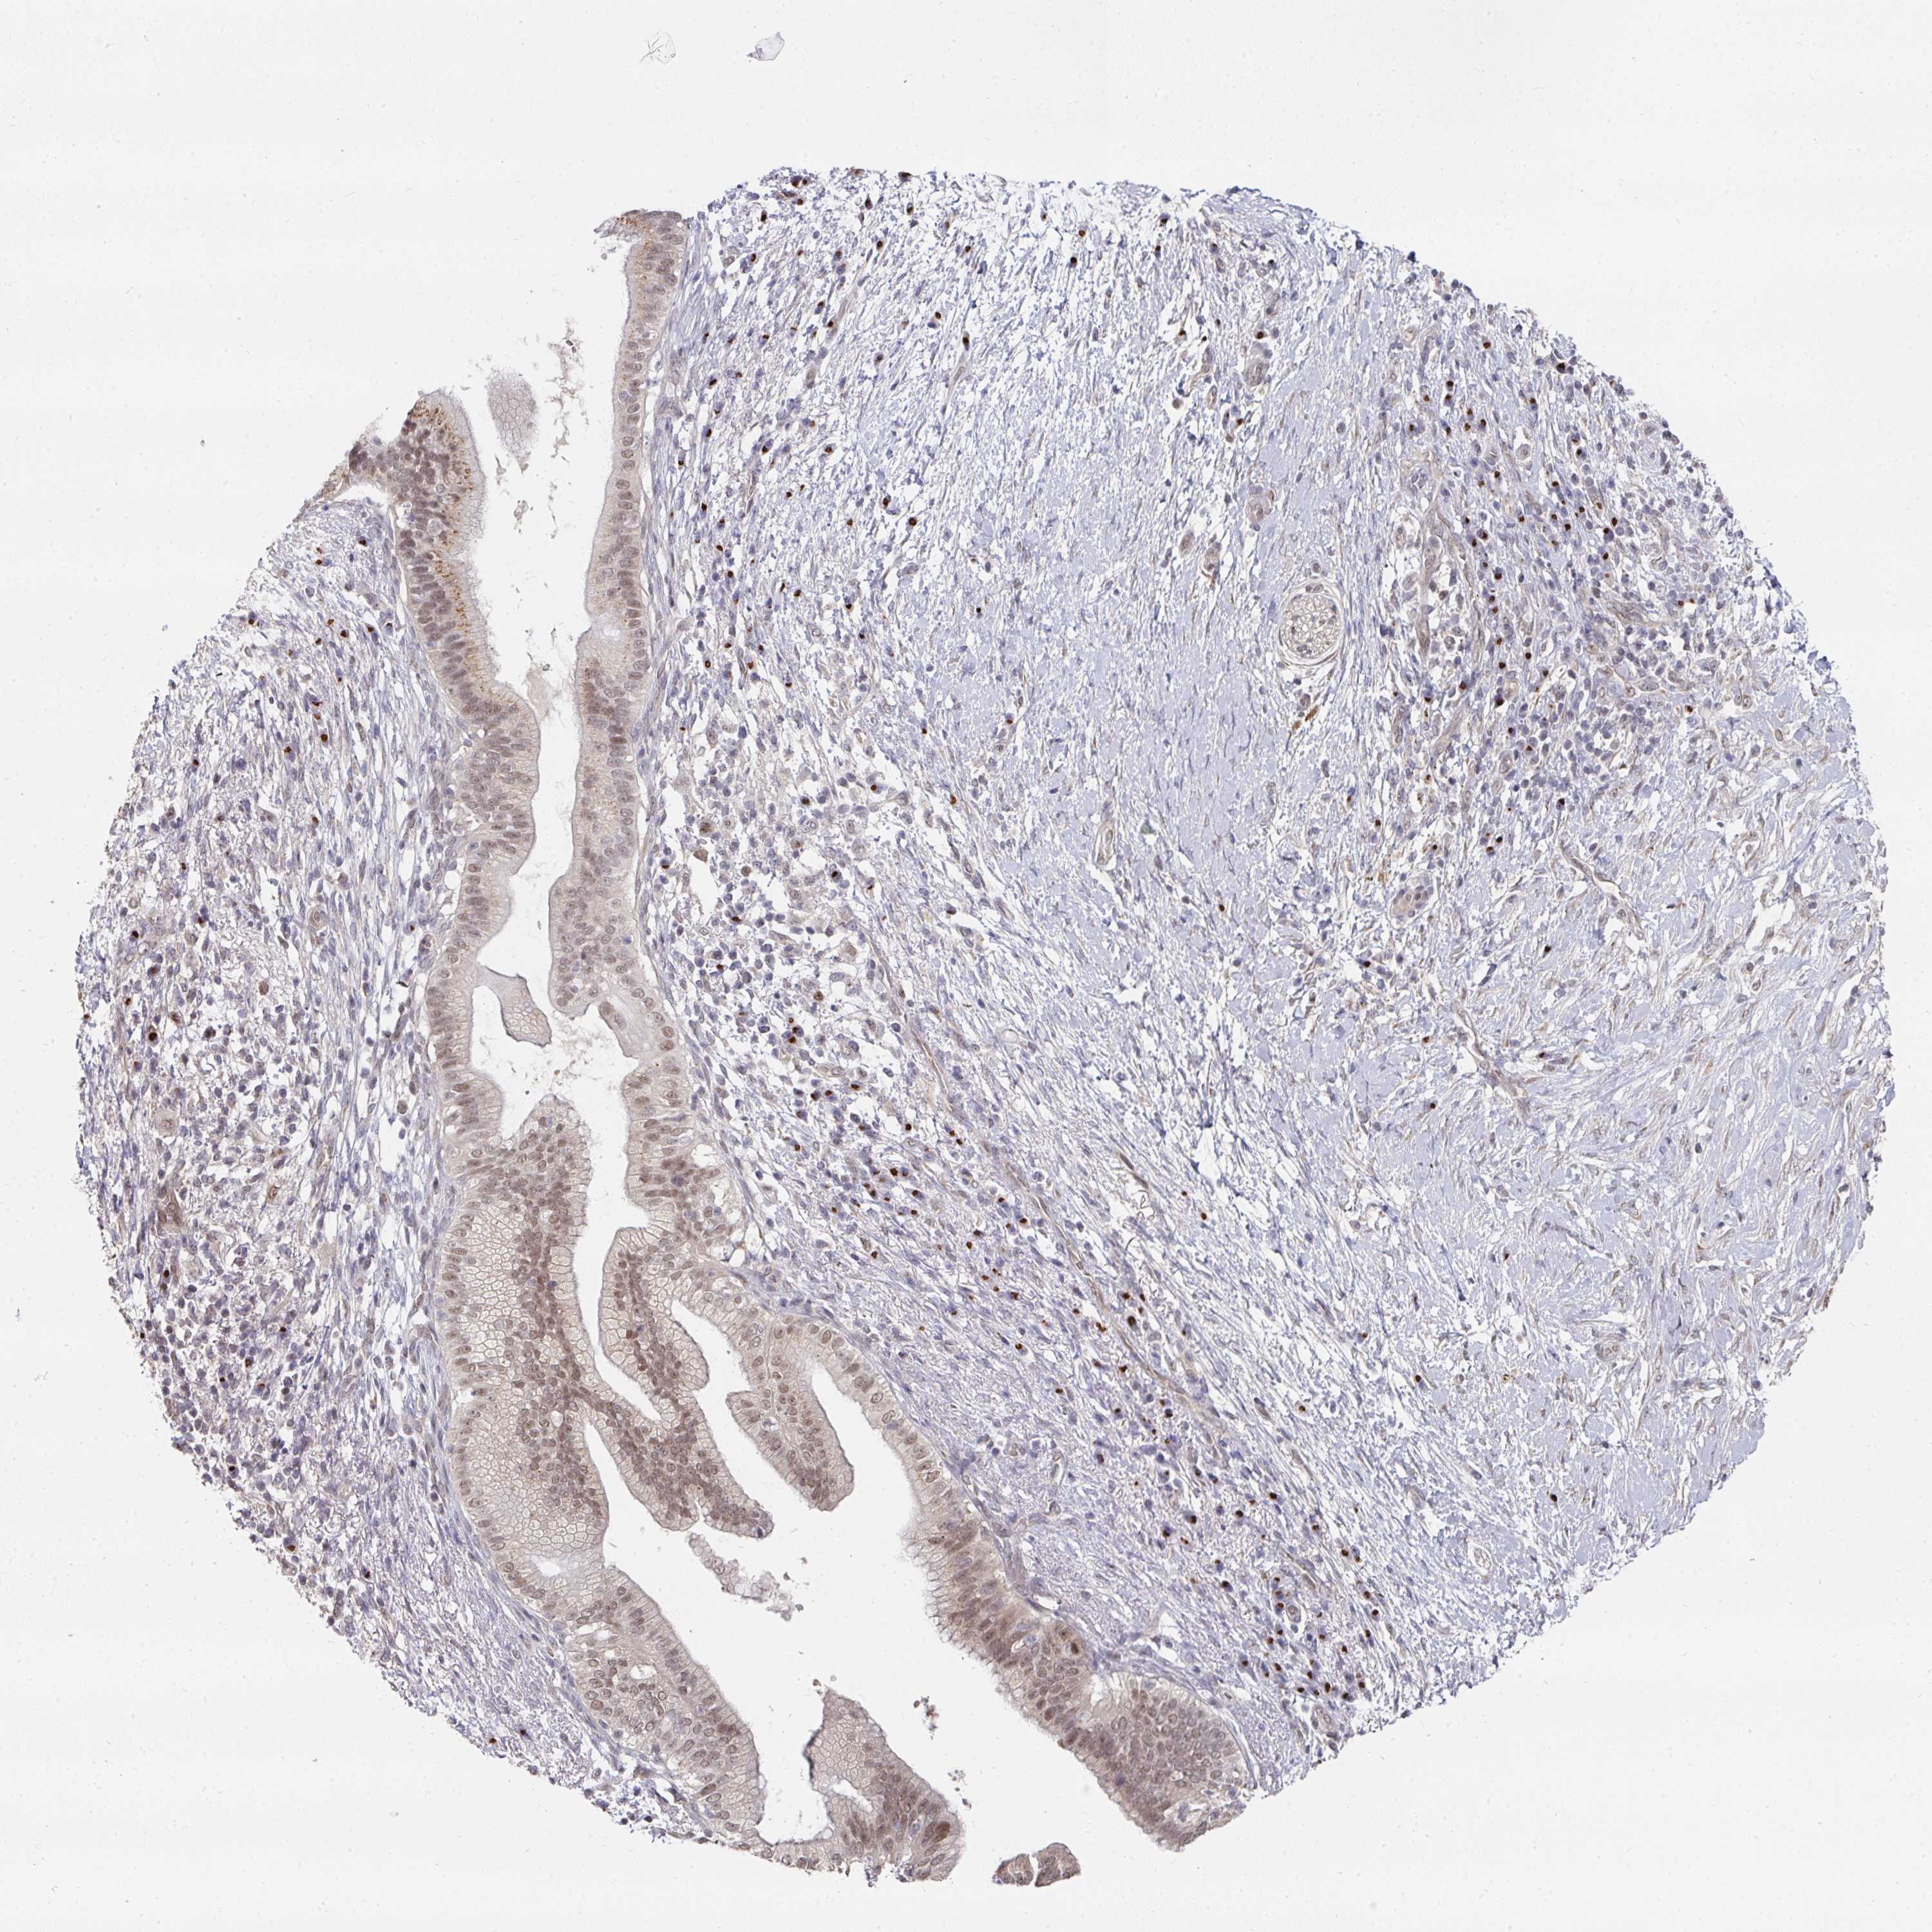

PANCREATIC CANCER - Protein expressioni

A mouse-over function shows sample information and annotation data. Click on an image to view it in a full screen mode. Samples can be filtered based on level of antibody staining by selecting one or several of the following categories: high, medium, low and not detected. The assay and annotation is described here.

Note that samples used for immunohistochemistry by the Human Protein Atlas do not correspond to samples in the TCGA dataset.

Antibody stainingi

Antibody staining in the annotated cell types in the current human tissue is reported as not detected, low, medium, or high, based on conventional immunohistochemistry profiling in selected tissues. This score is based on the combination of the staining intensity and fraction of stained cells.

Each image is clickable and will lead to virtual microscopy that enables deeper exploration of all samples and also displays staining intensity scores, fraction scores and subcellular localization as well as patient and tissue information for each sample.

Antibody HPA051314

Staining

High

Medium

Low

Not detected

Intensity

Strong

Moderate

Weak

Negative

Quantity

>75%

75%-25%

<25%

None

Location

Nuclear

Cytoplasmic/membranous

Cytoplasmic/membranous,nuclear

Adenocarcinoma, NOS